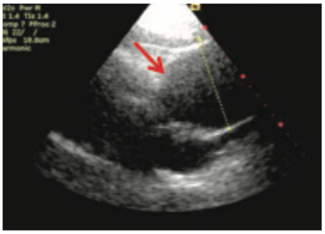

An ascending aortic aneurysm is an uncommon, incidental finding for patients undergoing transthoracic echocardiography (TTE) during an outpatient visit.

A 60-year-old female with no significant past medical history presented with recurring chest discomfort, elevated troponin, and systolic murmur.